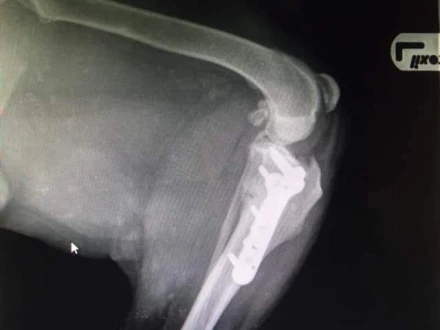

Operacje ortopedyczne:

Specjalizujemy się w szerokim zakresie operacji ortopedycznych, obejmujących leczenie złamań, problemów ze stawami, w tym operacje rekonstrukcyjne. Nasze zaawansowane techniki chirurgiczne zapewniają precyzyjne leczenie urazów i chorób układu ruchu.

Metoda TPLO